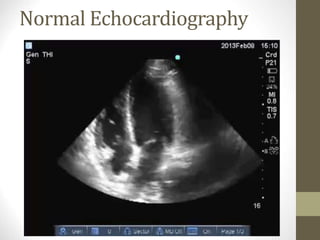

Normal Echocardiography

• Echocardiography and MRI are useful in

establishing the diagnosis.